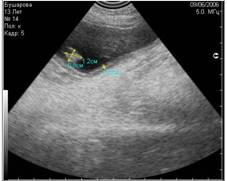

- вызванные недостаточным количеством УЗИ-геля, нанесённого на кожу (Рис.4) ;

Рис 4. Недостаточное количество геля при проведении УЗИ (правая половина снимка). |